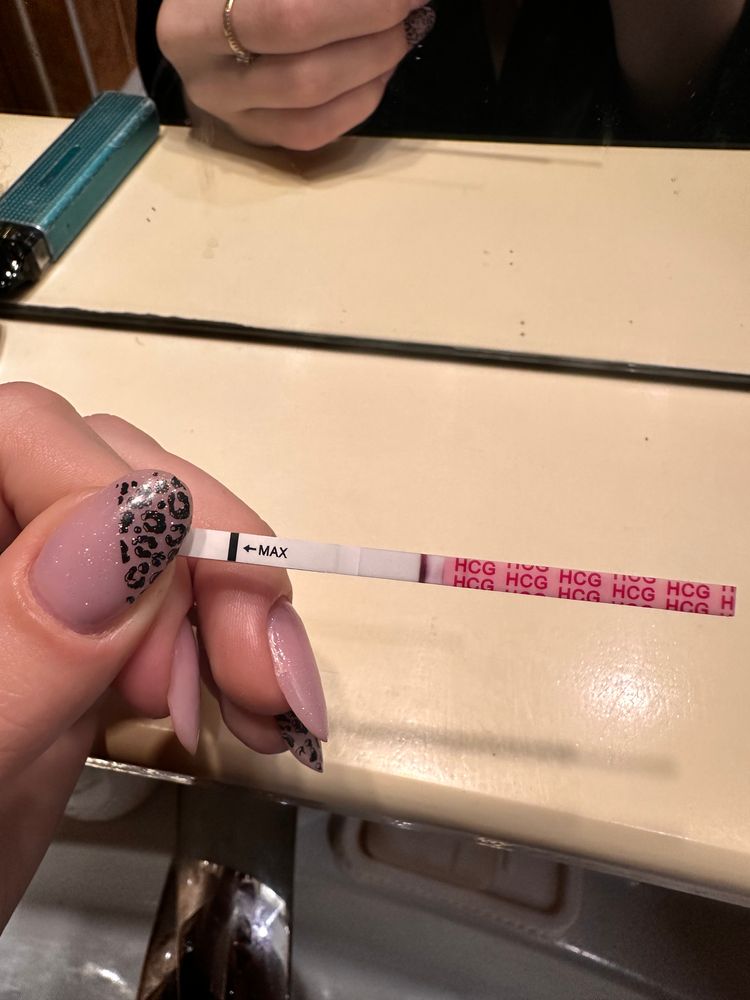

Овуляция была или ещё будет?

Как думаете, овуляция была уже? Если да, то на какой дц?

1 февраля тест положительный,значит была 1-3 февраля

Наталья, а почему тогда не снижается ЛГ, не знаете? На сколько я знаю, то должно снижаться.. вот Фемометр мне показывает сегодня пик🫠

Elena Krushelnytskaya, а от 1 числа что фемометр говорит?там самый яркий тест

Наталья, от первого тоже говорил пик, и тоже 200%🤔

я ради интереса несколько циклов после родов делала тесты на овуляцию, то после пика тесты тускнели.

Наталья, поэтому я и думаю что странный цикл, странные тесты, графики - не перерос ли фоликул в кисту. А то такое ощущение, что овуляция вот-вот наступит и не наступает (по тестах и графику). А вот симптомы все второй фазы (выделения, боль в груди, аппетит, усталость, головная боль)

Elena Krushelnytskaya, ещё я вчера вечером сделала тест на б, полоски не было и я его отложила.. а сегодня днем достала его и там жиирный реагент. Конечно я понимаю что не информативно и там 100% реагент был. Но цикл оооочень странный

Elena Krushelnytskaya, переделайте тест на беременность)))

Наталья, тест переделала сейчас - отрицательный(

про лг вот читала, поэтому такое ощущение, что фолликул перерос в кисту🥺

а у той девушки сразу после овуляции были положительные тесты на овуляцию?

Наталья, да, симптомы именно как во второй фазе, даже, простите, выделения желтоватые. Вот странно ещё, что часто бегаю в туалет пописять - такого не было, только в беременность.

раньше на 17-19 дц ловила пик

Elena Krushelnytskaya, может вторая овуляция?но полоска не такая яркая,как 1 февраля.Остается два варианта - или к врачу на прием или ждать монстриков и тогда все понятно будет

Elena Krushelnytskaya,

Если у женщины исходно повышен уровень ЛГ, тест может оказаться положительным. Такая ситуация наблюдается у пациенток с преждевременной недостаточностью яичников, а также в позднем репродуктивном возрасте, когда уровни гонадотропинов (ФСГ и ЛГ) изначально повышены.

Бывают ситуации, когда повышение уровня ЛГ начинается, но оказывается недостаточным. Овуляции не происходит, а преовуляторный фолликул преобразуется в фолликулярную кисту.

А ещё у девушки на форуме тесты на овуляцию были все время положительные и она оказалась беременной